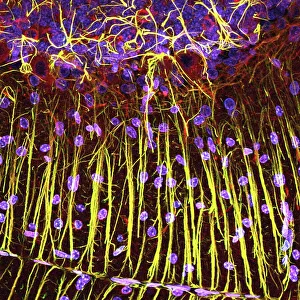

The central nervous system, the intricate network that governs our every thought and movement, is a marvel of complexity. From the delicate cerebellum tissue to the detailed light micrograph capturing its essence, we are reminded of its importance in maintaining balance and coordination. Anatomy comes alive as we explore the human brain from an inferior view. The intricacy of brain fibers is revealed through DTI MRI scans like C017/7099 and C017/7035, showcasing their vital role in transmitting information throughout this extraordinary organ. Artistic renderings bring us closer to understanding the medulla oblongata's significance within the brain. Its portrayal in various artworks allows us to appreciate how it controls essential functions such as breathing and heart rate. As we delve deeper into studying the central nervous system, models of the human brain provide invaluable insights into its structure and organization. Lateral views reveal countless regions responsible for cognition, emotion regulation, sensory perception, and motor control. Microscope slides offer glimpses into nerve cells' intricate architecture—a testament to their ability to transmit electrical signals at lightning speed. Meanwhile, glial stem cell cultures captured under a light microscope remind us of their crucial role in supporting neuronal function. Finally, artistic representations unveil the limbic system's enigmatic nature—an interconnected web responsible for emotions and memory formation. These captivating artworks allow us to visualize this complex network within our brains. Exploring these hints provides a glimpse into the awe-inspiring world of our central nervous system—the very foundation upon which our thoughts, actions, memories reside—reminding us just how remarkable our brains truly are.